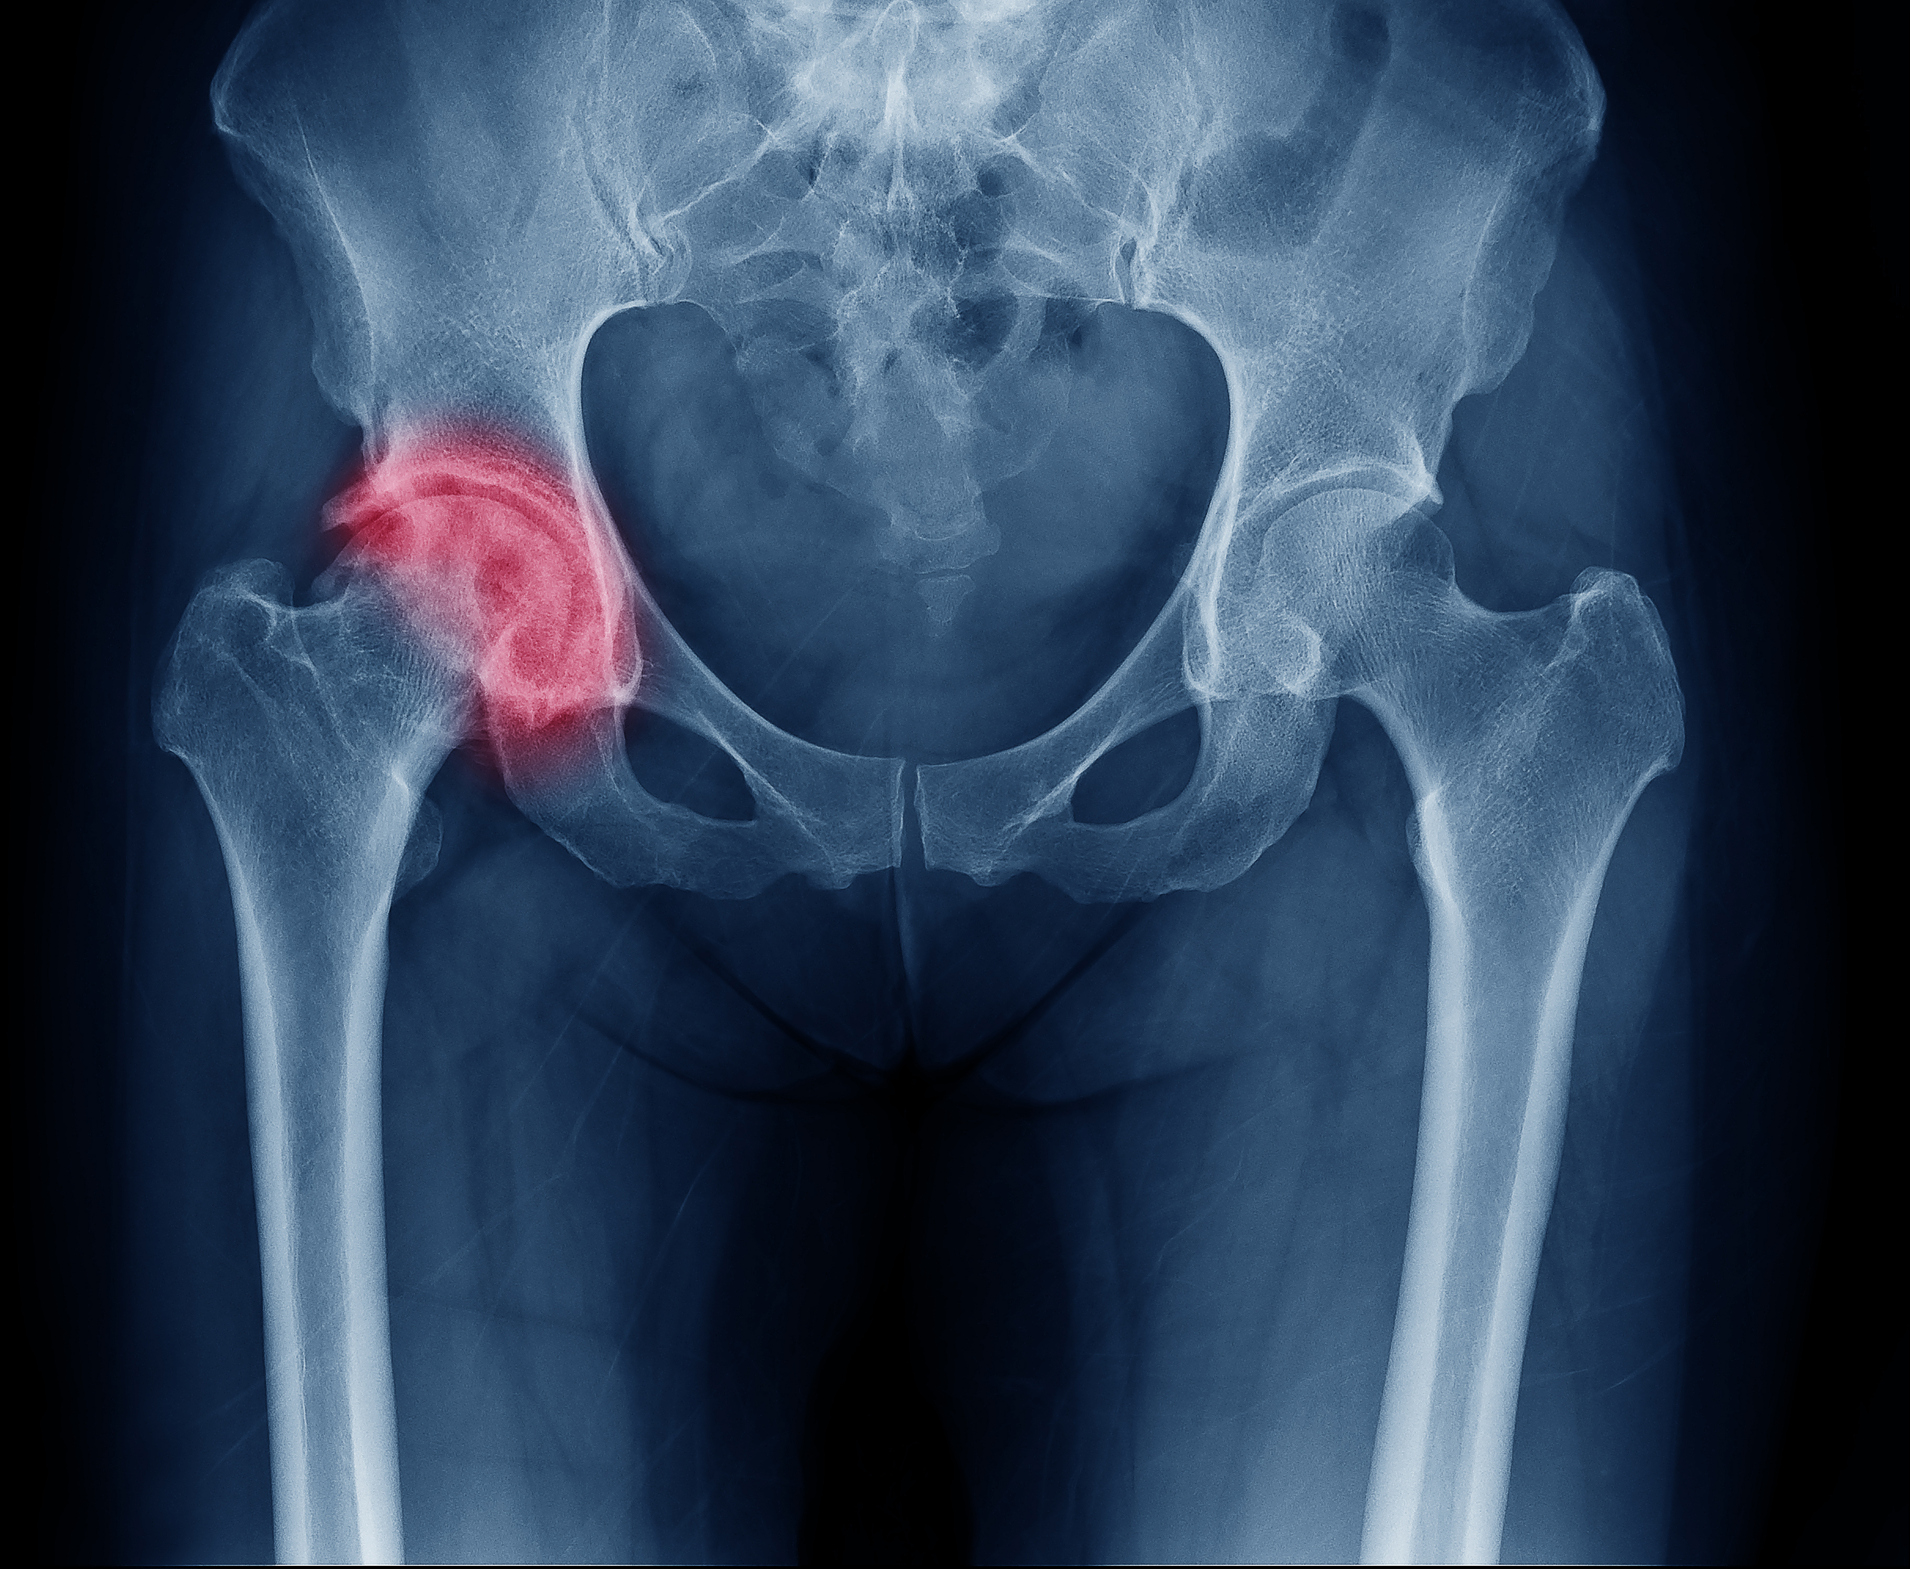

Фотографии и схемы: Коксит правого тазобедренного сустава